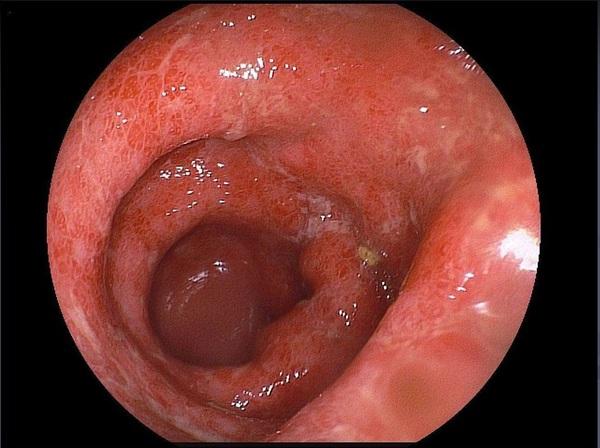

- колоноскопию с биопсией;

Преимущественно поражается прямая и сигмовидная кишка, заболевание протекает по типу колита. Пациента беспокоит частый жидкий кашицеобразный стул скудного объёма с обильными примесями слизи и крови (стул по типу “малинового желе”), наличие тенезм (болезненные и ложные позывы на дефекацию), а также императивные (неотложные) позывы на дефекацию. Характерно наличие болей в животе, чаще в нижней половине с левой стороны или болезненность в области заднего прохода.

- Амёбома - опухолевидное образование в стенке кишечника.